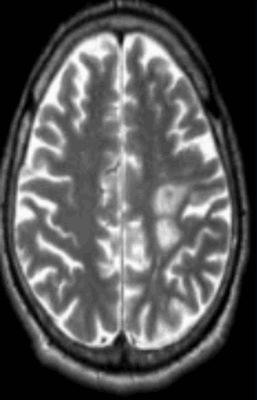

Острый рассеянный энцефаломиелит на МРТ

Если при МРТ головного мозга выявлены очаги, их расценивают как симптомы патологии органа. Зоны гипер- или гипоинтенсивного МР-сигнала свидетельствуют о нарушении структуры определенного участка церебрального вещества. Очаговые изменения могут быть единичными или множественными, крупными, мелкими, диффузными и т.п.. Подобное наблюдается при:

- энцефаломиелите и других заболеваниях.